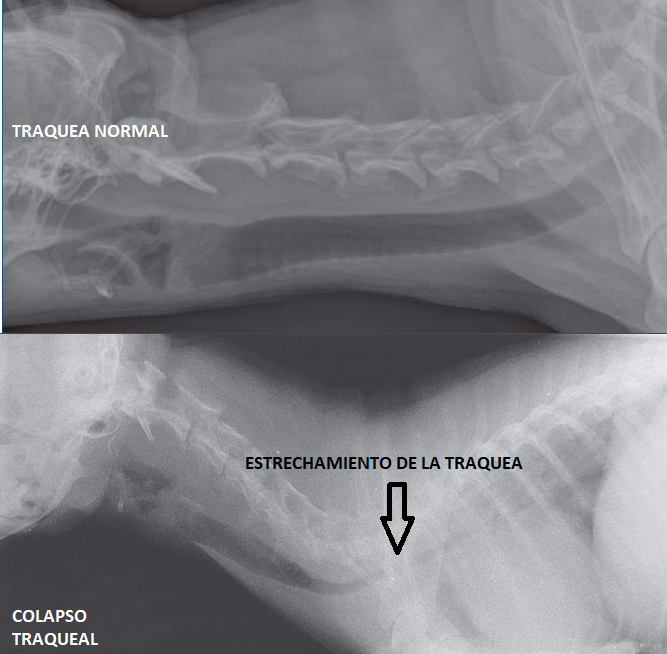

FOTO6

FOTO6.png